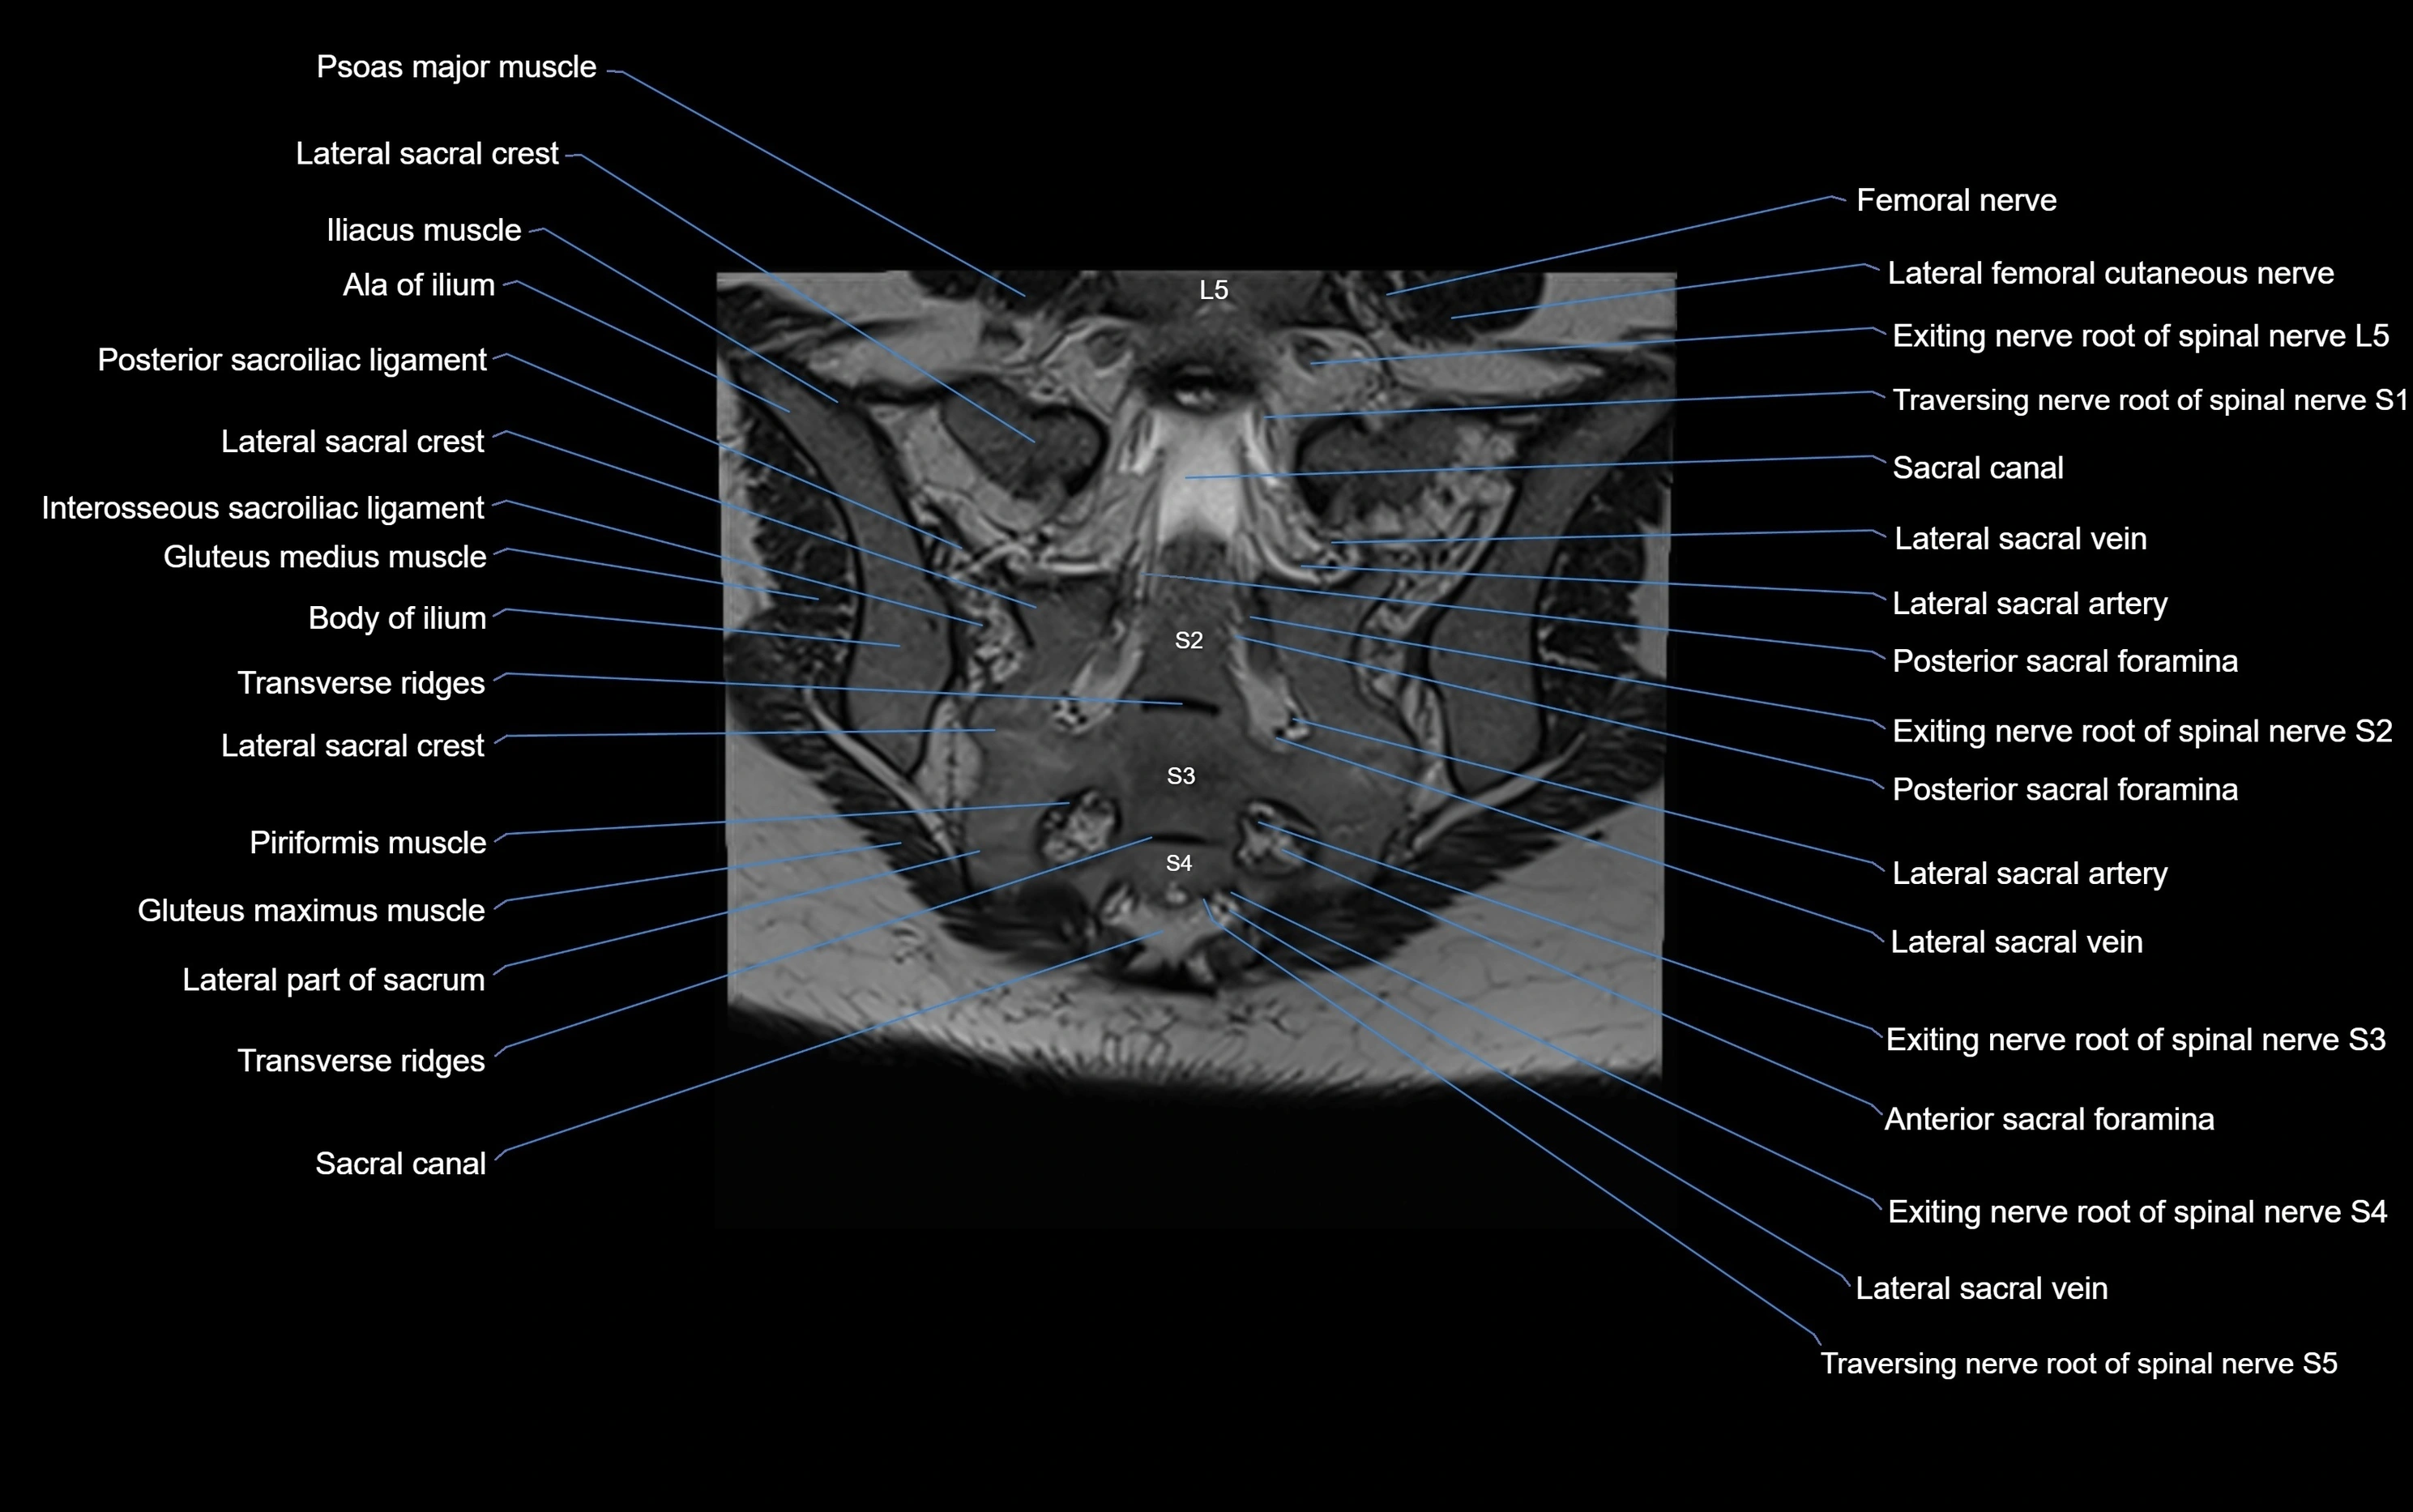

CT image

image